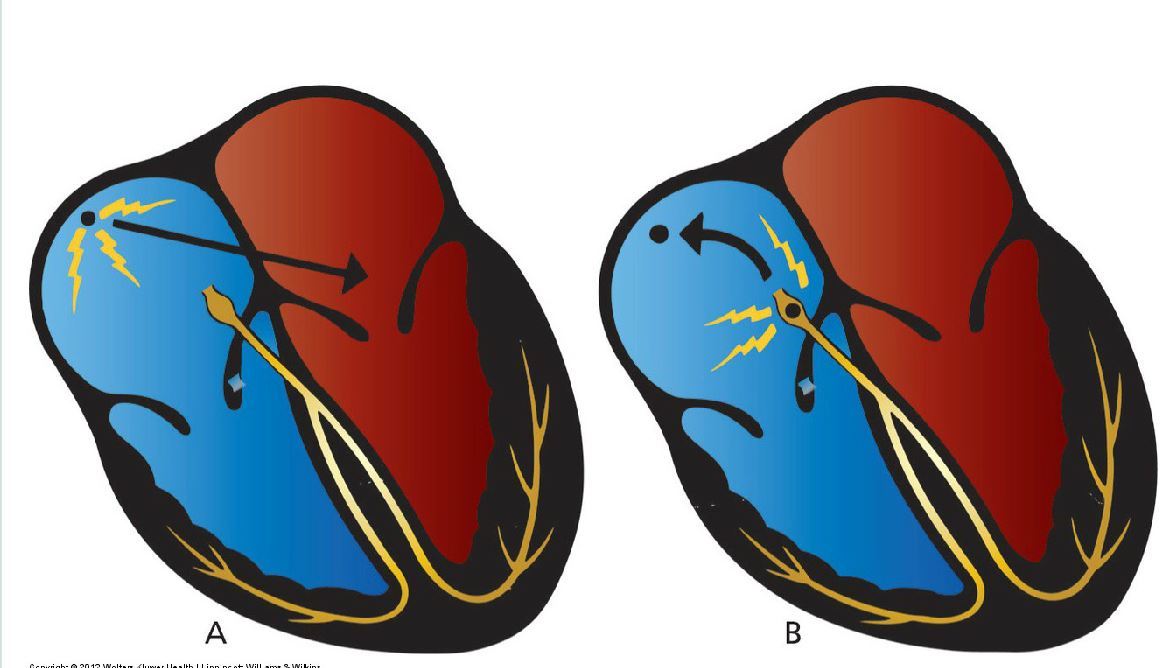

What does this illustrate?

(A) Normally, the sinus node drives the heart. (B) If another potential pacemaker (e.g., the AV junction) is accelerated, it can take over the heart and overdrive the sinus node.